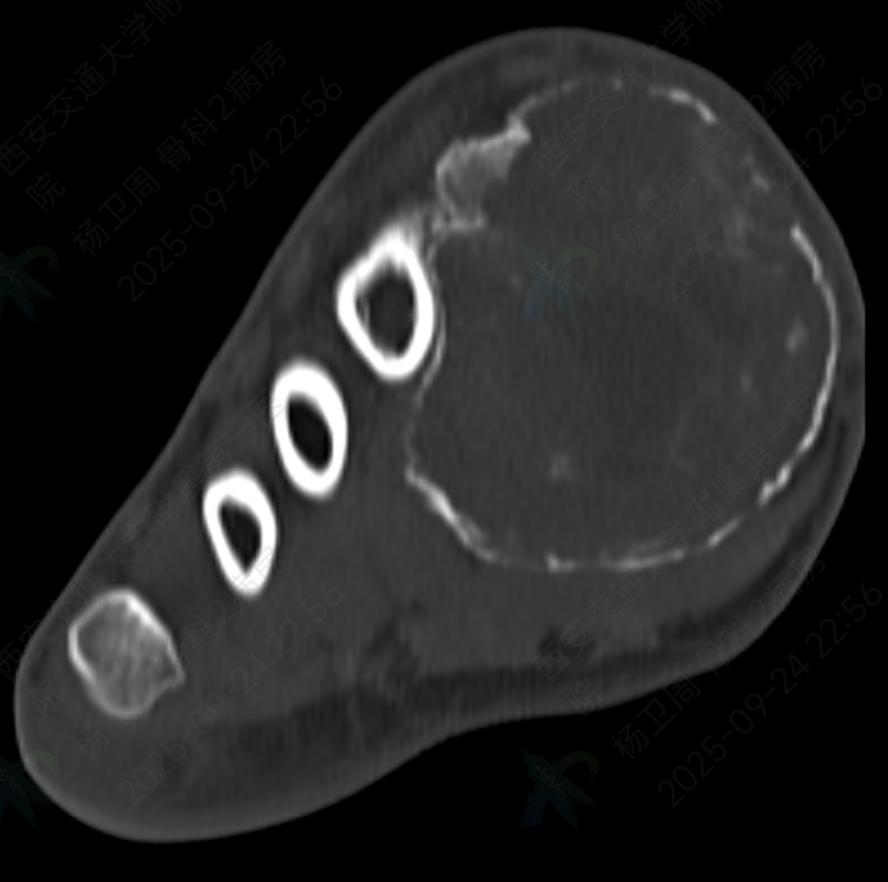

术前影像检查显示,肿瘤已严重破坏其内侧楔骨及第一跖骨,并形成一个被薄层骨壳包裹的巨大软组织肿块。治疗面临两难选择:若彻底切除肿瘤,将造成第一跖骨缺损,影响行走功能;而若仅行刮除术,则复发风险显著增加。面对这一复杂病例,韩学哲与边卫国教授迅速启动多学科协作机制,联合整形外科何林教授团队深入研讨,最终制定了“第一跖骨及内侧楔骨切除+带血管蒂腓骨移植重建”的手术方案。